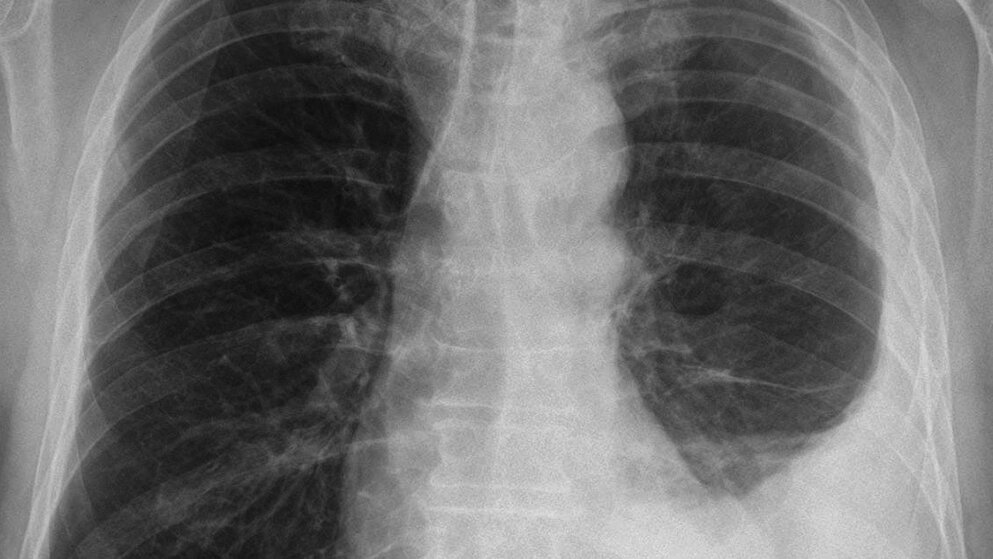

Die Therapie des Pleuramesothelioms erfordert die interdisziplinäre Zusammenarbeit von Onkologie, Chirurgie, Radioonkologie und Pneumologie. Daher ist der Patient mit Pleuramesotheliom am besten in einem Lungenkrebszentrum aufgehoben, da hier alle Fachrichtungen vertreten sind.

Schlüsselwörter: Pleuramesotheliom, Interdisziplinarität, Pleura visceralis, Pleura parietalis